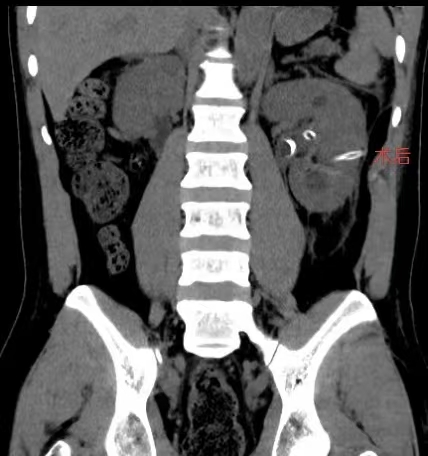

“腹部CT显示,患者左肾多发结石伴肾积水,且为多发鹿角形结石。”据朱澄村医生介绍,多发鹿角形结石是一种复杂肾结石类型,结石形状不规则,分支多,难以通过常规方法清除。

术后复查CT显示,Mohammed Rauf左肾结石被完美去除。看到复查结果后,Mohammed Rauf露出了开心的笑容,并竖起大拇指,对医院的医疗技术和医护人员的服务态度表示高度赞扬。

术后复查CT,Mohammed Rauf左肾结石完美去除。